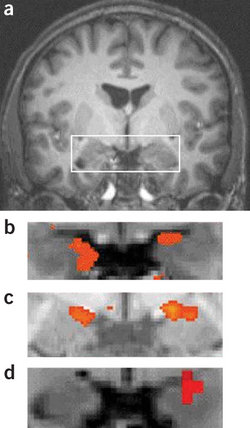

Figure 1: Contrast of viewing fearful and neutral faces. Large portions of occipitotemporal cortex are more strongly driven by fearful faces. The arrows point to the fusiform gyrus, a ventral temporal area that is strongly driven by face stimuli. Adapted with permission from the National Academy of Sciences: Pessoa et al. (2002b), copyright (2002).

Viewing emotion-laden visual stimuli is linked to heightened and more extensive visual system activation (Pessoa et al., 2002a; Vuilleumier, 2005). For instance, viewing faces with emotional expressions evokes increased responses relative to viewing neutral faces throughout ventral occipitotemporal visual cortex ( Figure 1).

Visual responses are also stronger when subjects view emotional scenes (e.g., a war scene) compared do neutral scenes (e.g., a lake scene). Increased visual activation is observed in both late visual areas, such as the fusiform gyrus and superior temporal sulcus, and early visual cortex in occipital cortex. Recent studies suggest that, in humans, even retinotopically organized visual cortex, including visual areas V1 and V2 along the calcarine fissure, are modulated by the affective significance of a stimulus (Padmala and Pessoa, 2008).